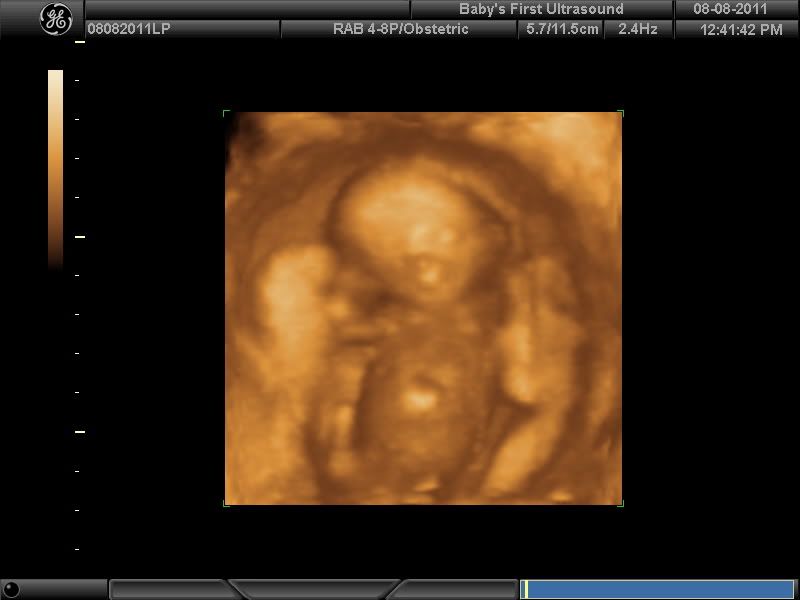

Now Introducing Lawson (PIP)

Wow Storm...it must be so exciting to see him growing all nice and baby-like :-)

Ha ha so that means I was looking at the wrong thing haha. So happy for you. The scans are awesome

Lawson is an awesome name.

Congratulations!!! I love that you are so super dooper excited.